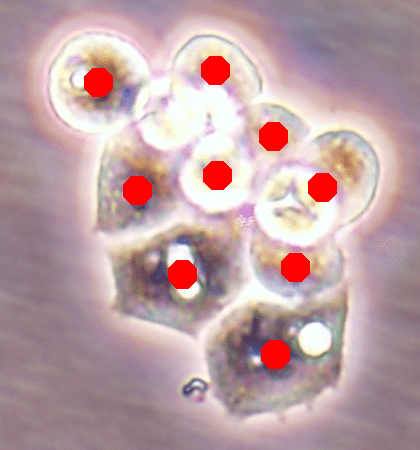

Before the advances in deep learning, the traditional approach for cell detection/segmentation is to employ low-level handcrafted features, reflecting color, edge, and shape characteristics of cells. This approach has given promising results when the features are defined properly, as a good representation of the visual cell characteristics. On the other hand, these characteristics may change from one cell type to another (see Fig. 1) and new features need to be defined to meet the cell characteristics of a new type. Additionally, when there exists heterogeneity in the visual characteristics of the same cell type, using a single model may not be sufficient to detect all cells of this type, particularly for cancer cells which are exploited more in high throughput screening.

![]() |

| (a) | (b) | (c) |

We test our DeepDistance model on three datasets, each of which consists of live cell images of a different cell line. They are the CAMA-1, MDA-MB-453, and MDA-MB-468 human breast cancer cell lines. The images in all datasets were acquired at magnification and pixel resolution. An example image from each dataset is shown in Fig. 1. As seen in this figure, cells might be visually different within and across different cell lines.